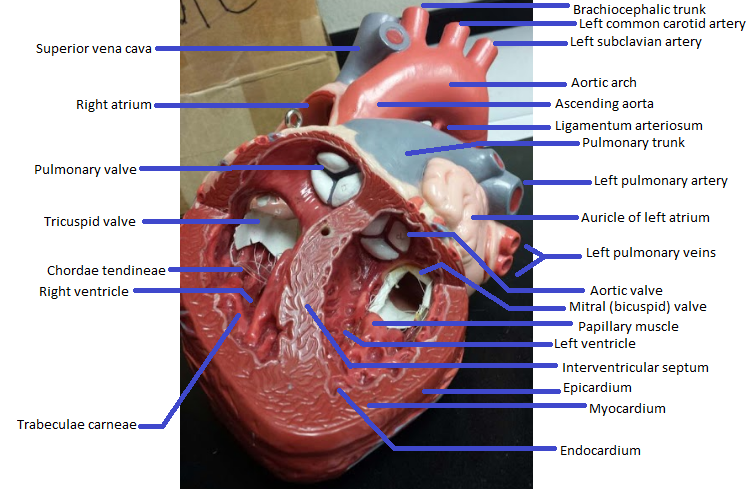

Name the missing parts.

Heart external anterior view